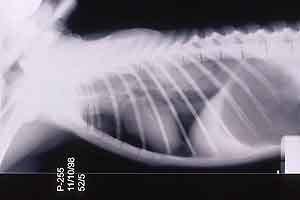

- Case 23-1. Chest radiograph. Diffusely lung fields

are infltrated by flocculent fluid densities.

- Case 23-3. The A/P thoracic radiograph shows marked

right sided deviation of the cardiac silouette. The lateral thoracic

- Thoracic radiographs demonstrated an increased pulmonary

interstitial pattern with air bronchograms bilaterally. The cardiac

silhouette was shifted to the right. Abdominal radiographs demonstrated